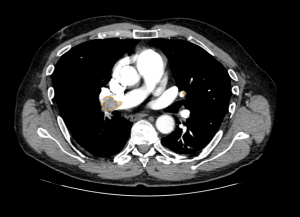

CT Eye™ is designed to assist radiologists reviewing adult chest CT studies by identifying radiological signs associated with pulmonary embolism (including incidental PE in contrast studies), lung nodules, and lung consolidation. The system helps prioritise studies where these findings may be present, provides study-level localisation of suspicious areas, and performs automated quality checks by comparing image content with the radiologist’s final report using integrated NLP analysis.